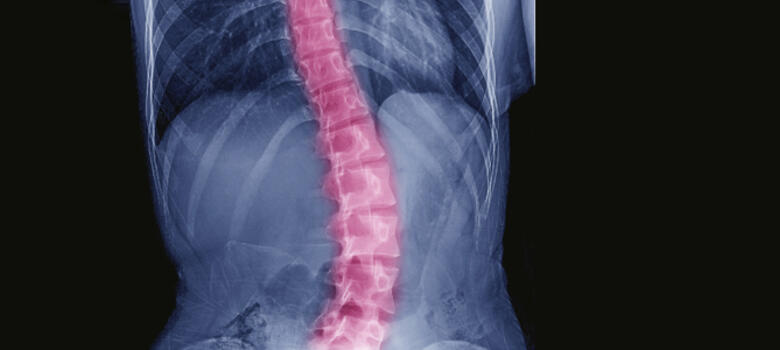

Revision Spine Surgery Restores Mobility After Multiple Spine Surgeries

Challenging procedure takes patient from wheelchair to fishing boat

After a series of spine surgeries left a 69-year-old man reliant on a wheelchair or cane, multiple centers were unable to help his complex case: a partially fused spine with a forward/side-leaning stoop which also compressed nerves, causing sciatic leg pain. Additionally, a previous weight-loss surgery complicated his presentation. The patient was no longer able to enjoy time with his grandchildren, fish on his boat, or take a walk on the beach with his wife.

After consulting several other surgeons who could not help him, the patient came to Brett Rocos, MD, for revision spine surgery. “No amount of physical therapy or increasing muscle strength would have been enough to correct this patient’s spine,” Rocos says. “We’re the last line for patients like this. Either we do it or no one does.”

In a nine-hour surgery, Rocos and the team began by removing previous devices from a lumbar fusion and a spinal cord stimulator. They then decompressed the spine and placed artificial bone grafts between the vertebrae. Using four cobalt rods and approximately 40 screws from T2 to the pelvis, the team pulled the patient’s spine straight. “We recreated normal spine anatomy as best we could,” says Rocos.

Rocos reports that the patient was able to stand the day after surgery. His healing was complicated by a serious infection, but Duke critical care and infectious disease teams coordinated with his previous weight-loss surgeon to provide high-quality care for a full recovery.